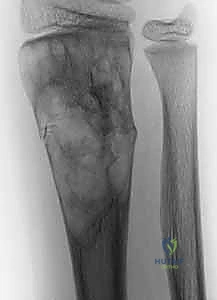

- الطبيعة: ورم حميد ولكنه عدواني محليًا بشكل شرس. يتميز بوجود خلايا عملاقة متعددة النوى تشبه ناقضات العظم (Osteoclasts) التي تدمر النسيج العظمي.

- الموقع المفضل: نهاية عظمة الكعبرة (Distal Radius) عند المعصم هي ثالث أكثر الأماكن إصابة في الجسم.

- السلوك السريري: ينمو بسرعة، يدمر القشرة العظمية، وقد يمتد إلى مفصل المعصم نفسه. على الرغم من أنه حميد، إلا أن لديه قدرة غريبة على إرسال نقائل (Metastasis) حميدة إلى الرئتين في حوالي 2% إلى 10% من الحالات.

- الأعراض: ألم مستمر يزداد مع الحركة، تورم ملحوظ في المعصم، وتحدد شديد في نطاق الحركة.

| شكل الأشعة السينية | تكلسات منقطة (Popcorn calcification) | فقاعات الصابون (Soap bubble appearance) | تجويف شفاف مركزي |

في حالات ورم الخلايا العملاقة (GCT) في المعصم: يفضل الدكتور هطيف استخدام الأسمنت العظمي (PMMA) لملء الفراغ، حيث أن الحرارة الناتجة عن تصلب الأسمنت تساهم في تدمير أي خلايا ورمية متبقية وتقليل نسبة ارتجاع الورم، كما يسمح للمريض بتحريك يده في اليوم التالي للجراحة.